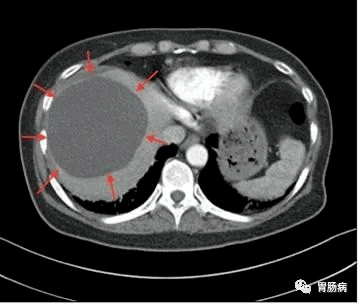

CT如下图所示

大多数肝囊肿无明显症状 , 仅在B超或CT检查时偶然发现 , 少数可表现为餐后饱腹感、食欲减退、腹痛腹胀等 , 尤其是体积较大的肝囊肿 。